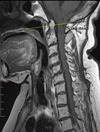

Artritis reumatoide

- Reconstrucción sagital de TAC

- Erosiones en odontoides y arco anterior de C1 con subluxación anterior C1-C2.

Artritis reumatoide

- Reconstrucción sagital de TAC

- Afectación de la columna cervical (erosiones, esclerosis, destrucción discal) con impresión basilar